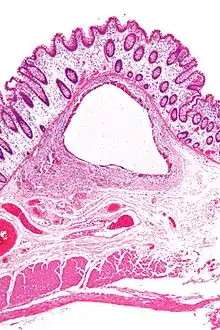

A lung cyst, or pulmonary cyst, encloses a small volume of air, and has a wall thickness of up to 4 mm.[3] A minimum wall thickness of 1 mm has been suggested,[3] but thin-walled pockets may be included in the definition as well.[4] Pulmonary cysts are not associated with either smoking or emphysema.[5]

A lung cavity has a wall thickness of more than 4 mm.[3]